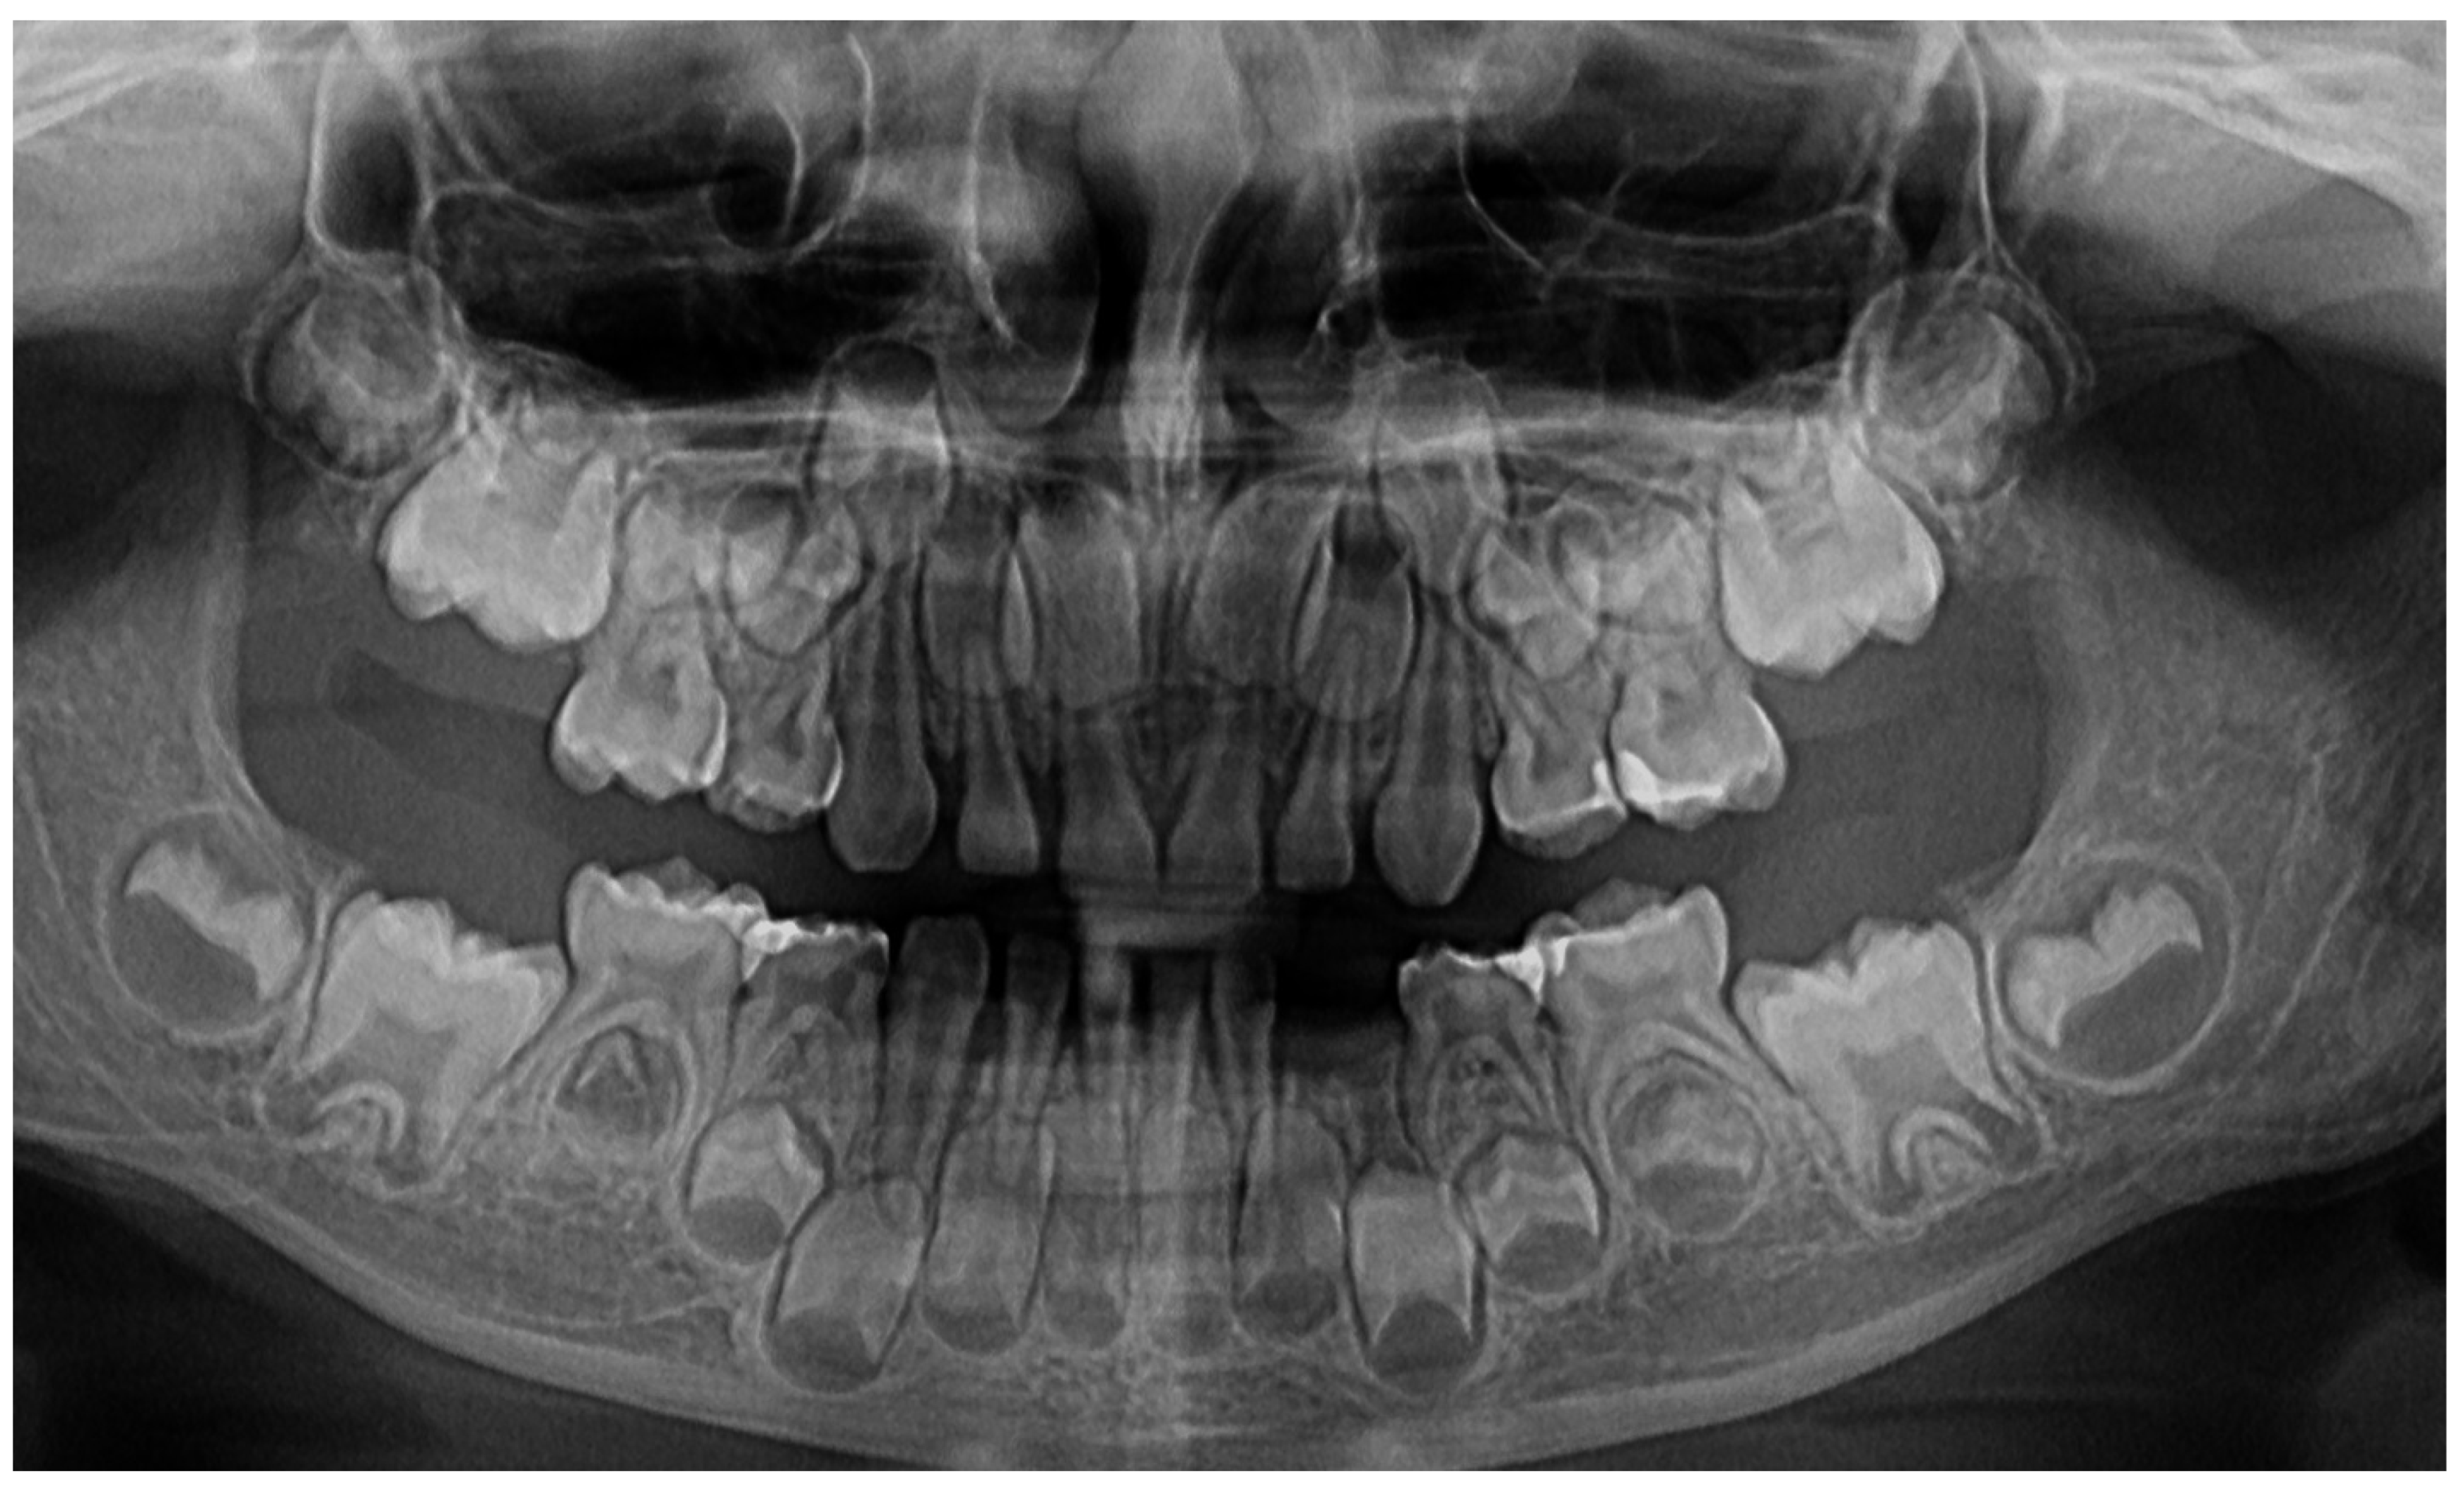

In M. University Hospital (Periodontology Department, Germany, 14 June 2023), a full oral clinical and paraclinical examination was performed including X-ray examinations (retro-alveolar and panoramic) (Figure 1). As a result, the deciduous left canine movement and a localized bone loss around the above-mentioned tooth were confirmed, with suspicion of a metabolic disease (i.e., hypophosphatasia/hyperphosphatasia), while the pain complaints were cataloged as of unknown cause. No other problems were identified (e.g., orthodontic disorders, hyper-eruption, etc.). The case was dismissed with no prescribed therapy, no clinical diagnosis, and only common oral hygiene instructions. The recommendations were to continue the investigations in the Endocrinology Department for blood count and genetic tests [1]. No periodontopathic bacteria test (that would significantly help in setting up the diagnosis) were proposed to the family, despite a clear picture of a localized periodontal disease in a pre-puberal patient (based on clinical examination and patient’s history).

The unusualness of this case is due to several aspects. The first is related to the extremely young age of the patient (i.e., 4 years old in February 2023, deciduous dentition), with an insidious onset, and apparently no familial aggregation or history. The second aspect is related to the misdiagnosis of metabolic diseases (i.e., hypophosphatasia/hyperphosphatasia as written) with oral manifestations (since no therapeutic measures were taken) despite the initial radiographical (i.e., Figure 1) and clinical examination that suggested a clear picture of an unusual LPP (e.g., the lower left canine involvement). The third aspect is related to the lack of therapeutic measures that rapidly set the course for the periodontal and 7.3 loss, in an interval of around 7 months (Figure 2) and the further progression involving other oral sites (Figure 3 and Figure 4). The fourth aspect is related to the evolution under adequate treatment (despite no written report to guide it) and the periodontal gain over a period of around 8 months following the antibiotic therapy (Figure 5 and Figure 6).

The clinical examination as well as the complementary radiological one could point out the LPP (localized pre-puberal periodontitis) diagnosis, despite the unusual involvement and limitation to deciduous canines (the literature reports the involvement of molars and incisors) [2,3,7,8,9,10,11,12,13]. The initial “U”-shaped bone loss [2,3,4,5,6] and limitation to the 7.3 site can easily exclude a general metabolic disease with oral manifestations (where usually there is no such limitation). The hypophosphatasia/hyperphosphatasia misdiagnosis (i.e., June 2023) can be easily rejected since the blood count and urine test displayed no such signs (i.e., high phosphate serum levels, low levels of parathyroid hormone due to hypercalcemia and hypercalciuria) [15,16,17,29,30]. The initial blood test (20 June 2023) revealed a slight increase in monocytes and lymphocytes, and a small decrease in neutrophile granulocytes, which are perfectly normal in a case of localized inflammation due to bacterial infection. The general form of prepuberal periodontitis related to systemic diseases (i.e., induce immunodeficiency affecting the response to the microbial plaque [15,16]) seemed not to be considered when the first clinical examination was performed (June 2023) even though hypophosphatasia is among the conditions with which the differential diagnosis can be made of.

Figure 1. First X-ray radiological investigations (14 June 2023): (A) panoramic with advanced periodontal loss around lower left canine, (B) retro-alveolar aspect of the 7.3 periodontal loss (München, Germany).